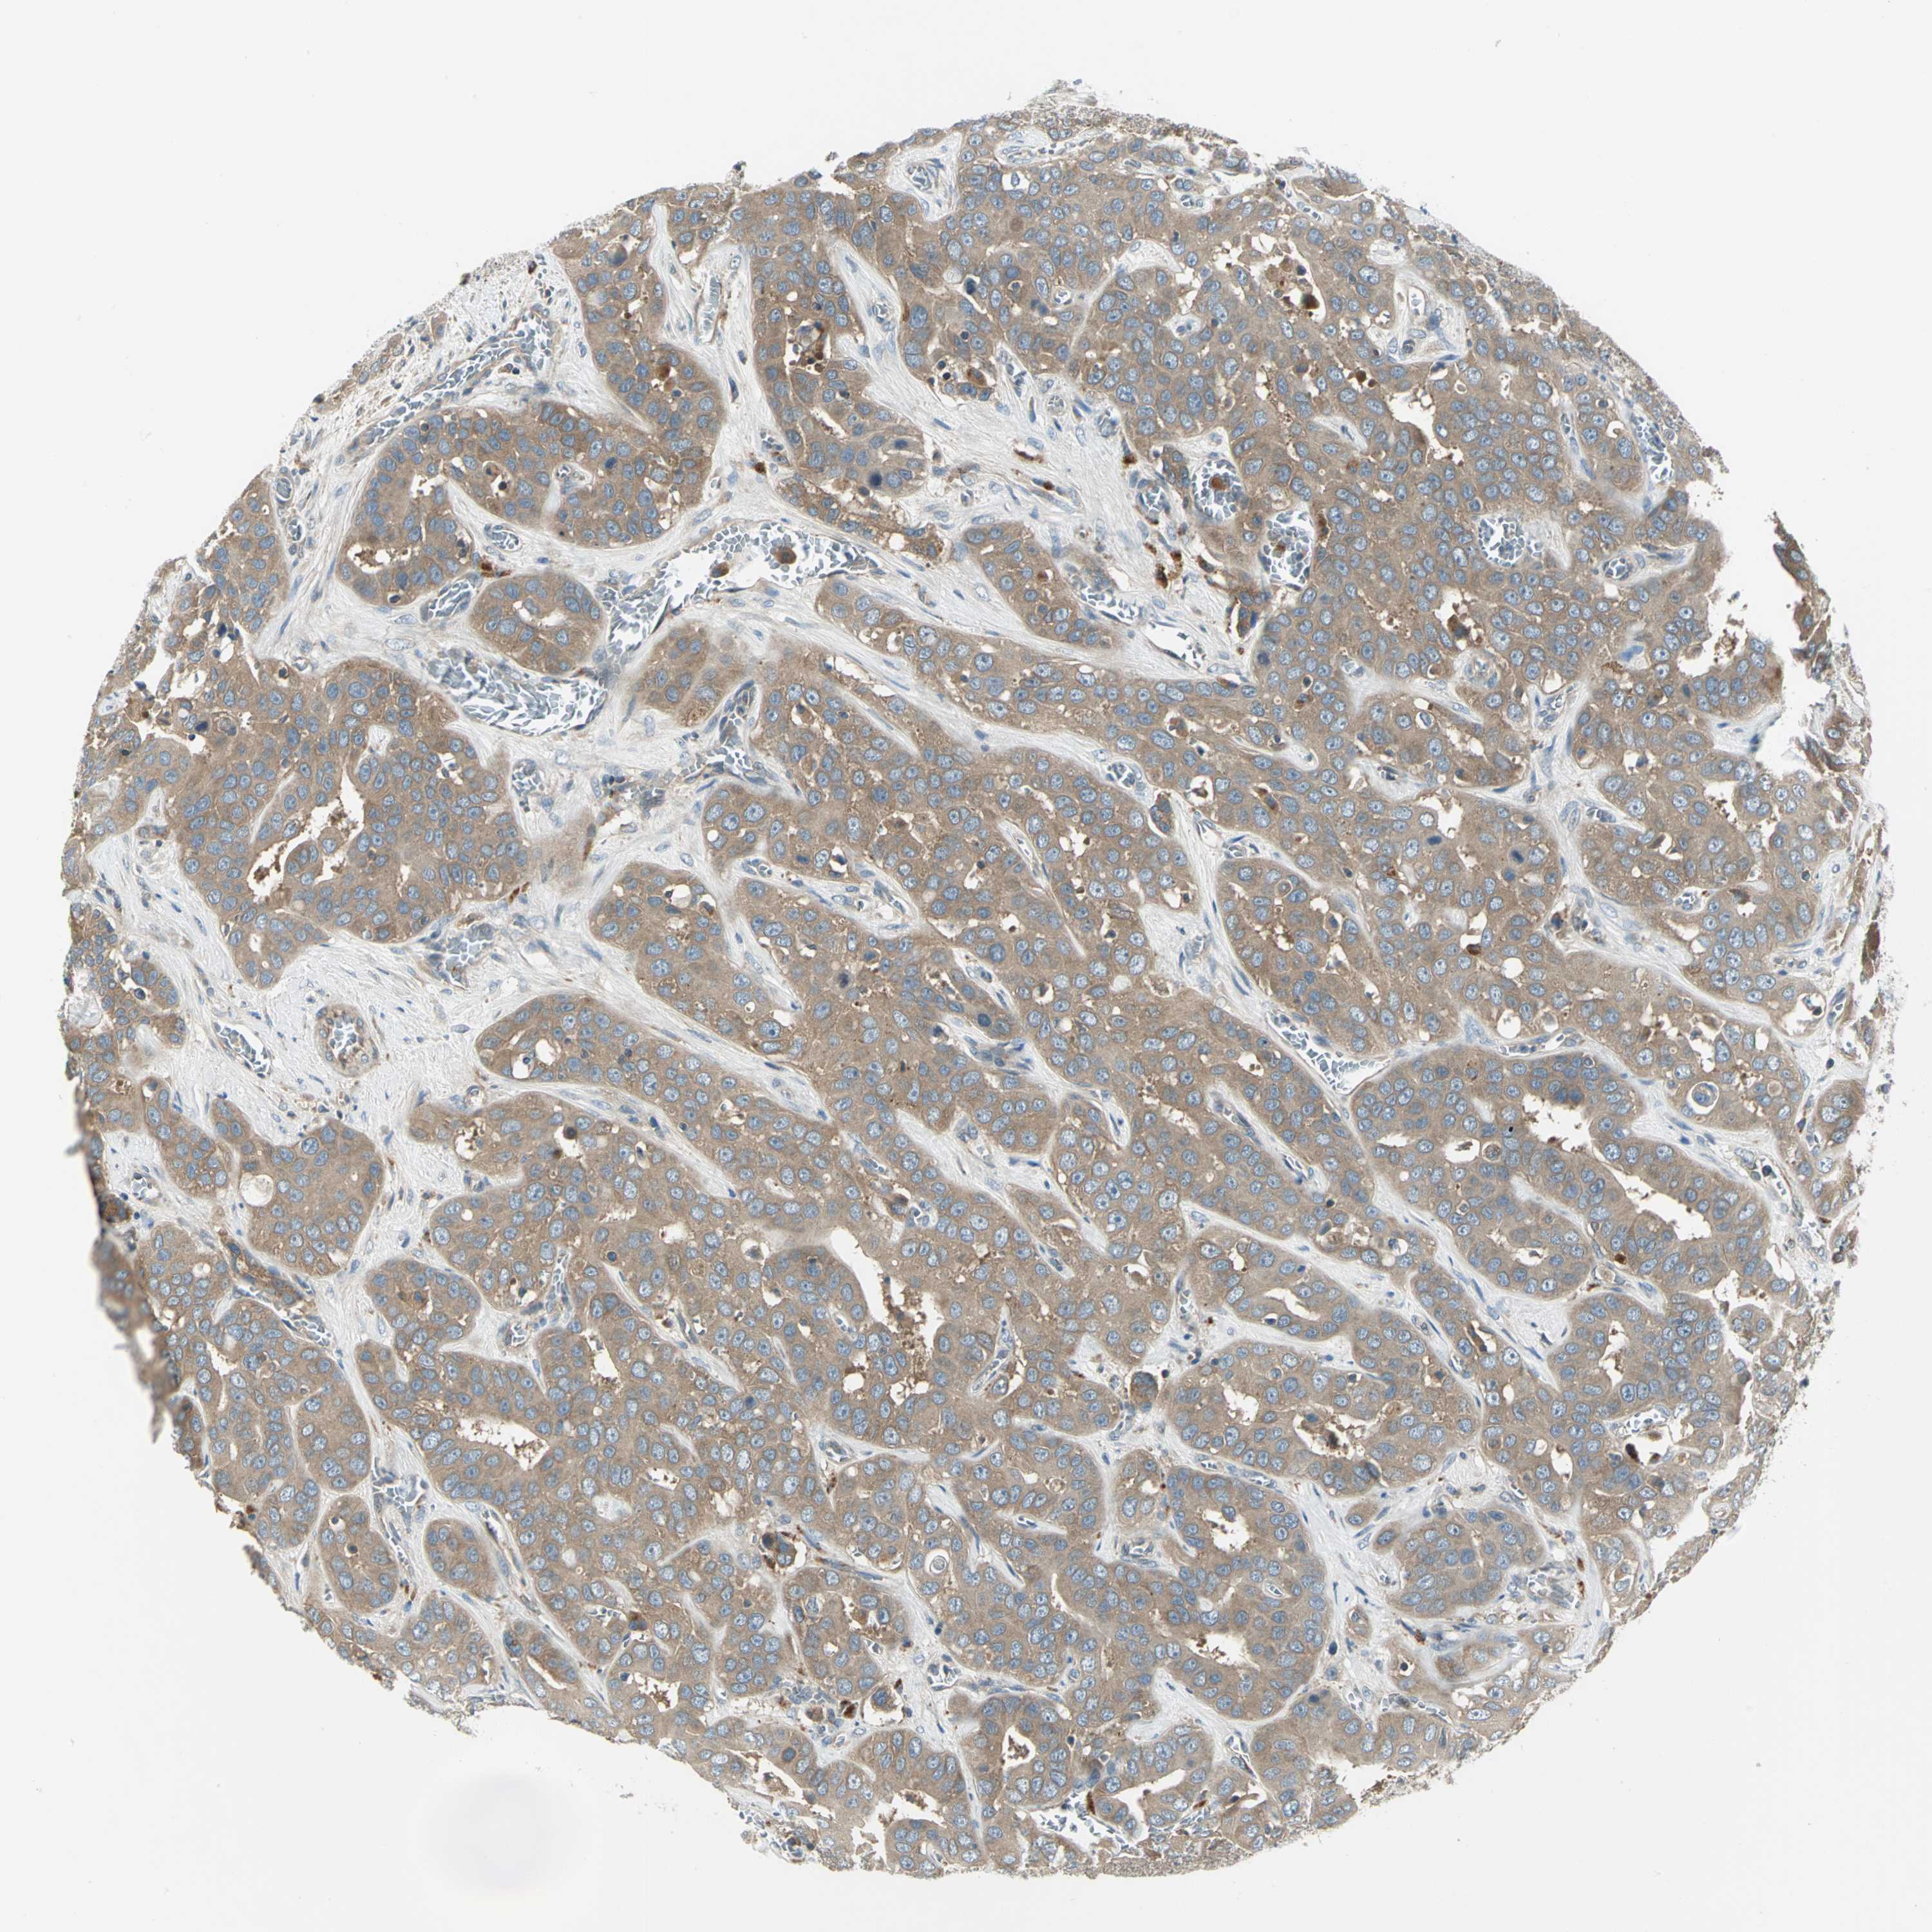

LIVER CANCER - Protein expressioni

A mouse-over function shows sample information and annotation data. Click on an image to view it in a full screen mode. Samples can be filtered based on level of antibody staining by selecting one or several of the following categories: high, medium, low and not detected. The assay and annotation is described here.

Note that samples used for immunohistochemistry by the Human Protein Atlas do not correspond to samples in the TCGA dataset.

Antibody stainingi

Antibody staining in the annotated cell types in the current human tissue is reported as not detected, low, medium, or high, based on conventional immunohistochemistry profiling in selected tissues. This score is based on the combination of the staining intensity and fraction of stained cells.

Each image is clickable and will lead to virtual microscopy that enables deeper exploration of all samples and also displays staining intensity scores, fraction scores and subcellular localization as well as patient and tissue information for each sample.

Antibody HPA064946

Antibody CAB005050

Staining

High

Medium

Low

Not detected

Intensity

Strong

Moderate

Weak

Negative

Quantity

>75%

75%-25%

<25%

None

Location

Nuclear

Cytoplasmic/membranous

Cytoplasmic/membranous,nuclear

Carcinoma, Hepatocellular, NOS

Cholangiocarcinoma